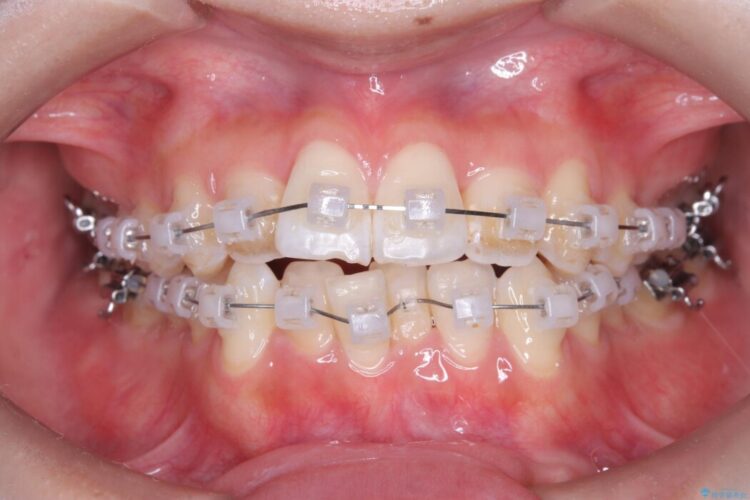

- 矯正装置:クリア装置 ワイヤー

歯の移動量や力のコントロールを最適化することで、短期間で治療完了しました。

「矯正は時間がかかる」というイメージをお持ちの方も多いですが、症例によっては、非抜歯でも短期間で改善が可能な場合があります。

治療後は歯並び・かみ合わせともに大きく改善し、患者様にも大変ご満足いただけました。